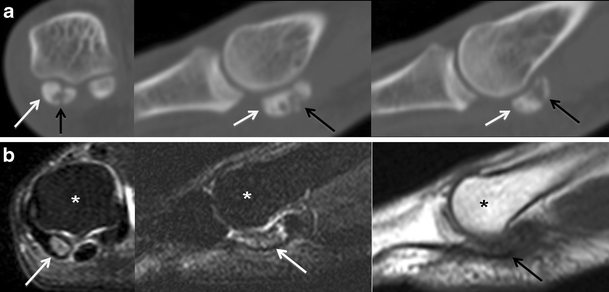

Osteonecrosis. a Short-axis and sagittal CT images depict a fragmented medial hallucal sesamoid (black arrows), with increased density of the fragments (white arrows) which suggests post-traumatic osteonecrosis. b Short-axis and sagittal T2-weighted fat-saturated MRIs, and sagittal T1-weighted MRI obtained 1 month later show a pattern of severe bone marrow oedema (white arrows) with T1 hypointensity (black arrow) isolated to the medial hallucal sesamoid, and further collapse of the medial hallucal sesamoid, consistent with progression of osteonecrosis. Note normal marrow signal in the first metatarsal head (asterisks)